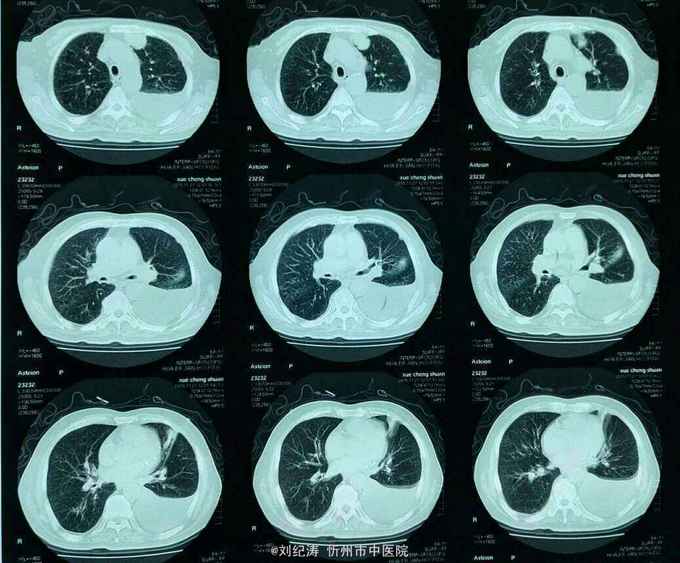

查体:ECOG评分:3分,生命指征平稳,浅表淋巴结未触及明显肿大,双眼睑无水肿,唇无发绀,颈软,双侧胸廓对称,左肺语颤增强,左肺呼吸音消失,右肺呼吸音粗,可闻及哮鸣音,心律齐,腹平软,肝脾肋下未触及,移动性浊音阴性,肠鸣音3次/分,双下肢无水肿。 辅助检查:血常规(2016.1.1):WBC:10.6*109/L,RBC:4.69*1012/L, PLT:165*109/L ,HGB:167g/L.生化(2016.1.1):谷丙转氨酶11U/L,谷草转氨酶11U/L,总蛋白60g/L,白蛋白33g/L,尿素:9.8mmol/L,肌酐:123umol/L,尿酸:251 umol/L,血糖:7.37 mmol/L;电解质:钾:4.79mmol/L,钠:123.5 mmol/L,氯:85.7 mmol/L,钙:2.03 mmol/L。肺部CT(2016.1.1):左肺完全萎缩,左侧胸腔大量积液,右肺未见异常,纵膈轻度右移,未见明显肿大淋巴结。